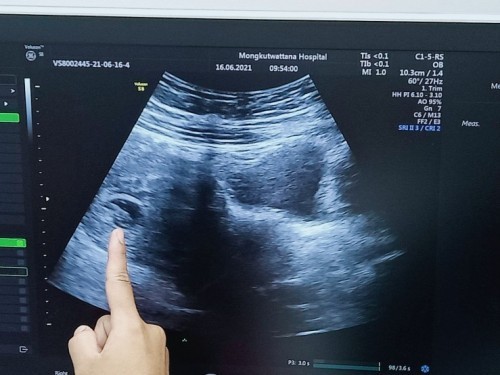

เจอตัวน้องตอน 7 สัปดาห์ 6 วันค่ะ เป็นกำลังใจให้แม่ๆทุกคนด้วยนะค่ะ

บ้านนี้จะไปฝากตอน 7 วีค 2 วัน หวังว่าจะเจอตัวน้องแบบนี้บ้างค่ะ 😂

ป่าวจ้า เพิ่งไปตรวจและฝากครร เลยค่ะ เจอตัวน้องเลย ตอนแรกกะกังวลค่ะ ว่าจะไม่เจอ เพราะอ่าน ในนี้เยอะมาก